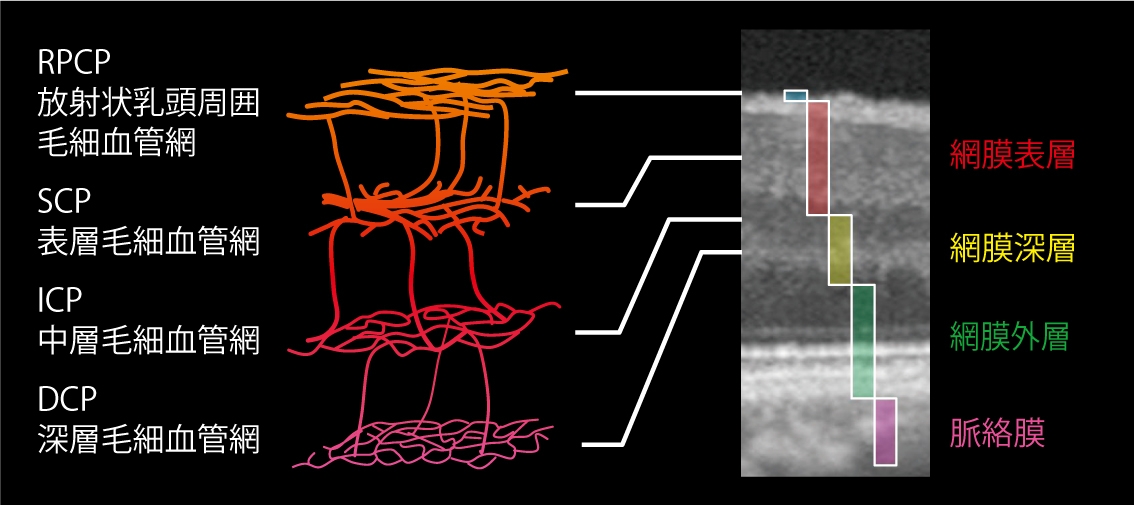

- CT-Angiographyにより、非侵襲で網膜毛細血管を各層別に観察可能(オプション)

任意設定により5種類(初期設定:網膜全層、表層、深層、外層、脈絡膜)のパノラマが同時に自動合成できます。

網膜表層 |

網膜深層 |

網膜外層 |

脈絡膜 |